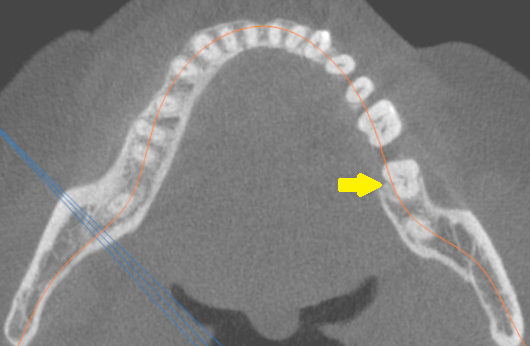

Prezentowany przypadek jest ciekawy głównie ze względu na obecność kanału typu C w pierwszym zębie trzonowym żuchwy. Tego typu anomalia dotyczy bowiem zazwyczaj drugiego zęba trzonowego żuchwy (ryc. 1) (1-3). Natomiast w pierwszym zębie trzonowym żuchwy występują z reguły trzy kanały: dwa bliższe i jeden dalszy. Choć niekiedy stwierdza się odmianę cztero- lub pięciokanałową – wówczas poza wymienionymi kanałami występuje w zębie drugi kanał w korzeniu dystalnym i/lub kanał dodatkowy pomiędzy kanałami bliższymi, który nosi nazwę kanału pośrodkowego (kanał bliższy pośrodkowy, MM) (4).

Ryc. 1. Badanie CBCT  żuchwy – przekrój poprzeczny. Strzałką zaznaczono drugi ząb trzonowy żuchwy z kanałem typu C.